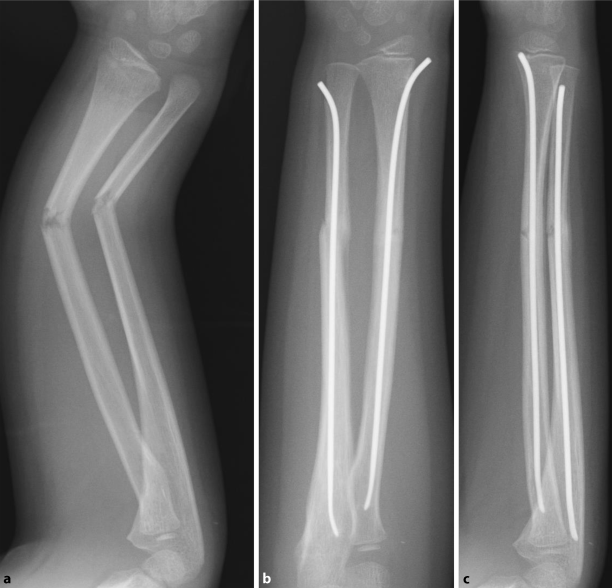

• Unterarmschaft Springerlink

Unterarmschaft Springerlink Reinhold Naegele